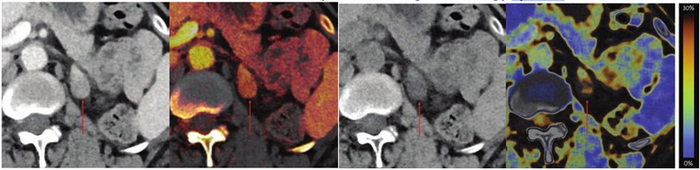

Leesburg, VA, December 1, 2022 According to an open-access Editor’s Choice accepted manuscript published in ARRS’ American Journal of Roentgenology ( AJR ) , for adrenal lesions evaluated by single-phase dual-energy CT (DECT), fat fraction had higher sensitivity than virtual noncontrast attenuation at both the clinically optimal threshold and at the traditional ≤10 HU threshold.

In this AJR accepted manuscript , 128 patients (82 women, 46 men; mean age, 64 years) who underwent portal-venous phase abdominopelvic CT between January 2016 and December 2019 showed a total of 139 adrenal lesions with a reference standard based on imaging, clinical, and pathologic records: 87 adenomas, 52 nonadenomas (48 metastases, 2 adrenal cortical carcinomas, 1 ganglioneuroma, 1 hematoma). Two radiologists located ROIs to determine virtual noncontrast attenuation, fat fraction, iodine density normalized to portal vein, and relative enhancement ratio—for masses with virtual noncontrast attenuation >10 HU.

Ultimately, for adrenal masses assessed by single-phase portal-venous phase DECT, when maintaining 100% specificity, sensitivity for adenoma was significantly higher for fat fraction [59% (95% CI: 48-69%)] than for virtual noncontrast attenuation at clinically optimal threshold [39% (95% CI: 29-50%)] or at traditional ≤10 HU threshold [28% (95% CI:19-38%)].